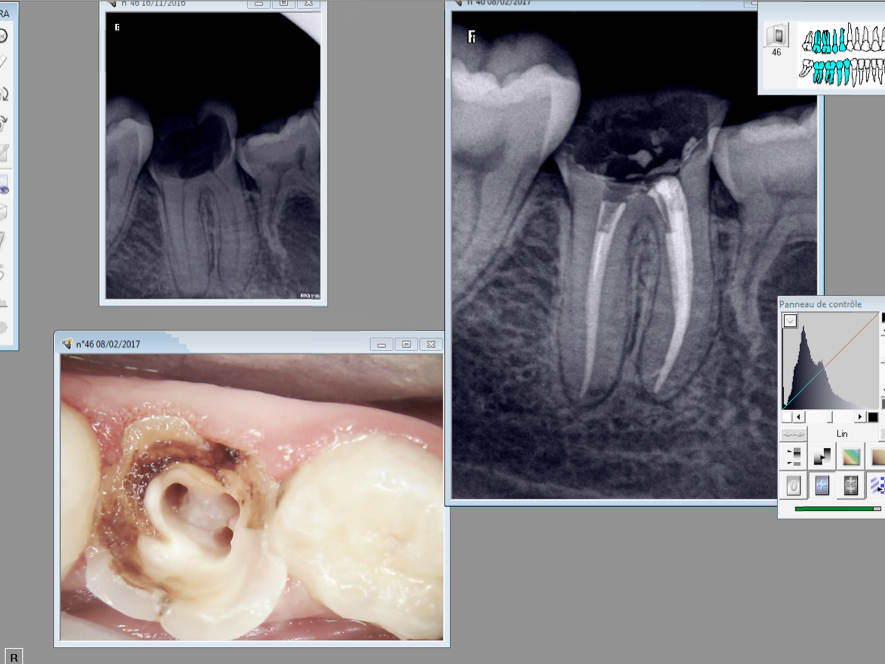

X séances d'une heure pour trouver les orifices, avec de la patience souvent on y arrive.

Là c'était pas trop difficile, pulpite aiguë, pas de souci d'AL normal, tronculaire... en plus avec la digue et un cavit bien étanche après l'obturation canalaire, zéro problème.

pulpite 16 ; 4 canaux tres difficiles dixit cbct

20 minutes pour trouver les 4 entrées (même la palatine était très difficile)

lachmar très content de lui se frise les moustaches en se disant qu'il est aussi bon que chicot

et paf un S1 gold dans le 2eMV (un tout neuf pour ce canal)

ca démotive )))

PS : pas de digue parce que sinon tu trouves rien (même la chambre pulpaire a été difficile à determiner )

PPS : 3 litres d'hypo, alors ca sera surement un succès quand même